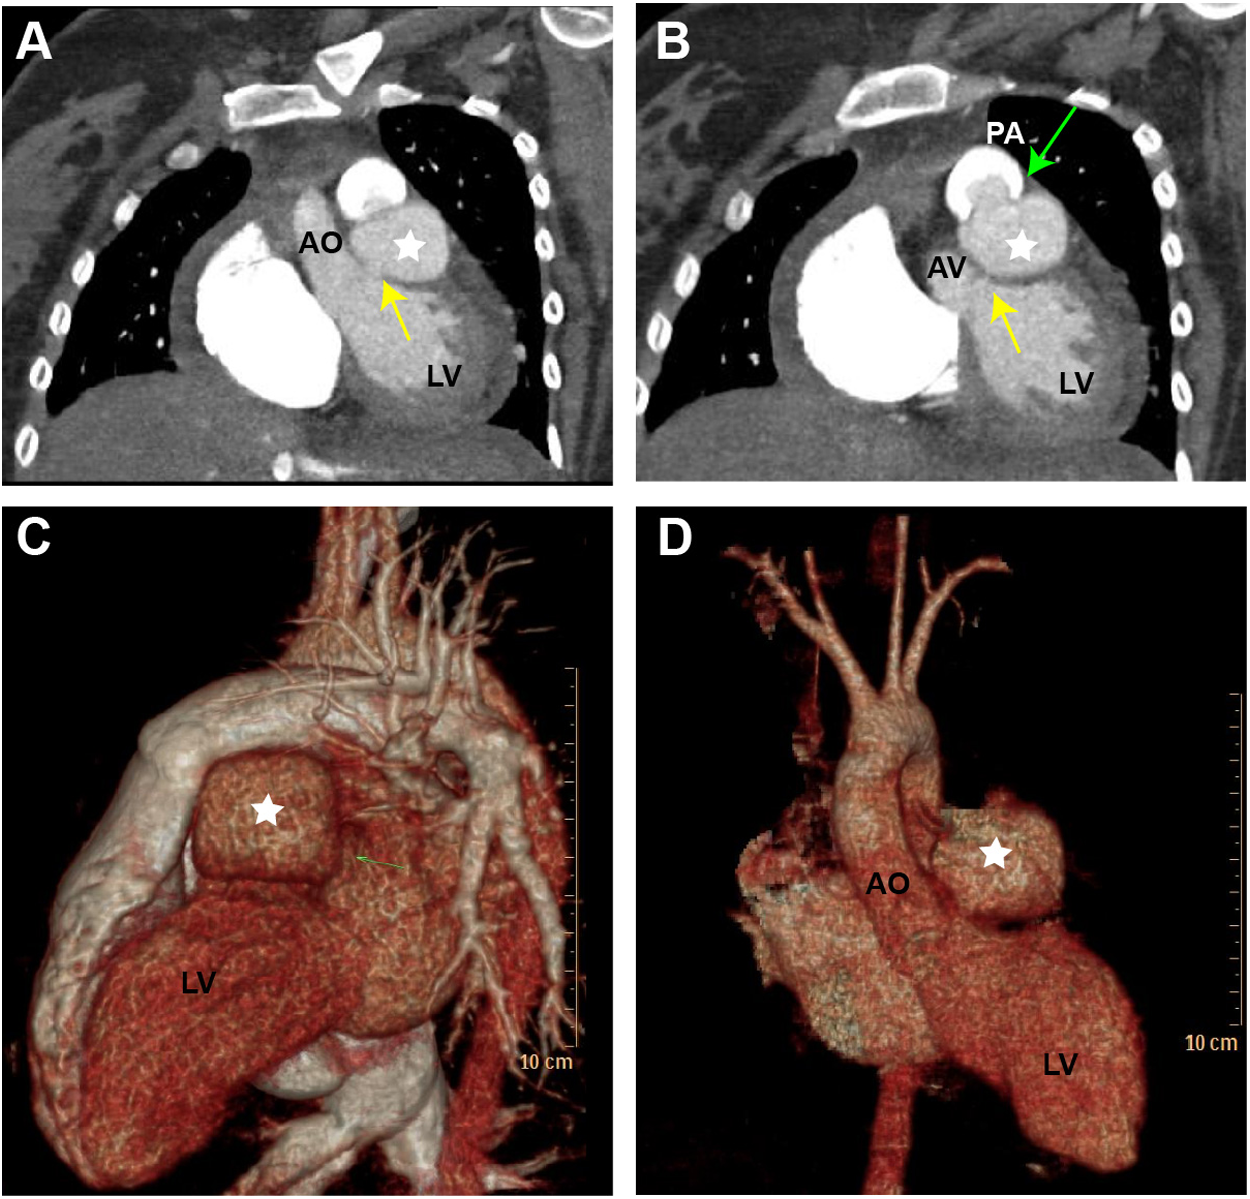

TTE revealed the presence of a left atrium and left ventricular enlargement, a left ventricular ejection fraction (LVEF) of 64%. We misdiagnosed the cystic structure communicating with the aorta through a channel with a width of approximately 7 mm on the side wall of the aortic valve ring (Figures 1A–C); and another communication port with a width of approximately 10 mm was also observed at the top of cystic structure, which connected to pulmonary artery (Figures 1D,E). The morphological changes of the cystic structure were not significant with respect to the contraction of the heart. Color Doppler imaging revealed that blood flowed through the communicating port into the capsule cavity during systole. Subsequently, the blood enters the pulmonary artery. Due to the presence of left to right shunting from the left ventricle to the pulmonary artery, the blood flow velocity in the pulmonary artery trunk increases rapidly, presenting a colorful mosaic-like blood flow signal (Figure 1F). CTA misdiagnosed as a SVA, approximately 4.1 × 3.2 cm in size, the width of the traffic area was approximately 8 mm (Figure 2). The main pulmonary artery was slightly widened, with a diameter of approximately 3.0 cm. Well visualization of the ascending aorta, descending aorta, left pulmonary artery, right pulmonary artery, brachiocephalic trunk, left common carotid artery, and proximal left subclavian artery, with smooth lumens and no stenosis or dilation. Digital subtraction angiography (DSA) revealed no significant stenosis or dilation in the right or left coronary arteries, and DSA suggested the presence of the diverticulum (Supplementary Figure S1). After completing relevant examinations after admission, including laboratory examination results exhibited elevated levels of some biomarkers like leukocyte (11.61 × 109/L; reference value 3.5∼9.5 × 109/L), C-reactive protein level (54.17 mg/L; reference value 0.068∼6.2 mg/L), hypersensitive troponin T (491 μg/L; reference value < 0.014 μg/L), N-terminal forebrain natriuretic peptide BNP (2,741 ng/L; reference value < 300 ng/L). Hepatitis B, hepatitis C, HIV antibodies and syphilis spirochete specific antibodies were negative and the patient's electrocardiogram results showed sinus rhythm. There were no obvious surgical contraindications, and she planed to undergo left ventricular diverticulectomy and pulmonary artery repair surgery. During surgery, a cystic diverticulum could be observed on the lateral wall of the left ventricular outflow tract (Figure 3A), extending toward the pericardial cavity and pulmonary artery. A communication port of approximately 8 mm (located below the aortic annulus) could be observed on the lateral wall of the left ventricular outflow tract and a rupture with a diameter of approximately 1 cm at the top of the capsule (Figure 3B; Supplementary Figure S2), communicating with the pulmonary artery. A continuous suturing technique using a 5-0 Prolene thread was employed to suture the communication port of the left ventricular outflow tract and the port of pulmonary artery rupture. Postoperative pathology revealed no epithelial lining in the capsule wall tissue. Myocardial cell atrophied and fibrosised, with some hyaline degeneration and local mucinous degeneration, consistent with changes in ventricular diverticulum (Figures 3C,D). After the surgery, the patient did not complain of any special discomfort. Her vital signs were stable, and her respiratory sounds were clear through auscultation in both lungs, without any dry or wet rales. There was no obvious murmur in the heart valves, and there was no swelling in the limbs. Postoperative echocardiography demonstrated that the left ventricle was still dilated, and the diverticulum collapsed without any residual shunts (Supplementary Figure S3).

Figure 2

Computed tomography angiography (CTA) and three-dimensional computed tomography (3D-CT) scan of the LVD. (A) Display the cystic structure between the aorta and pulmonary artery (yellow arrow). (B) The cystic structure protrudes into the pulmonary artery (green arrow). (C,D) The 3D-CT scan illustrates the LVD in different views (white star). LV, left ventricle; AO, aorta; AV, aortic valve; PA, pulmonary artery.